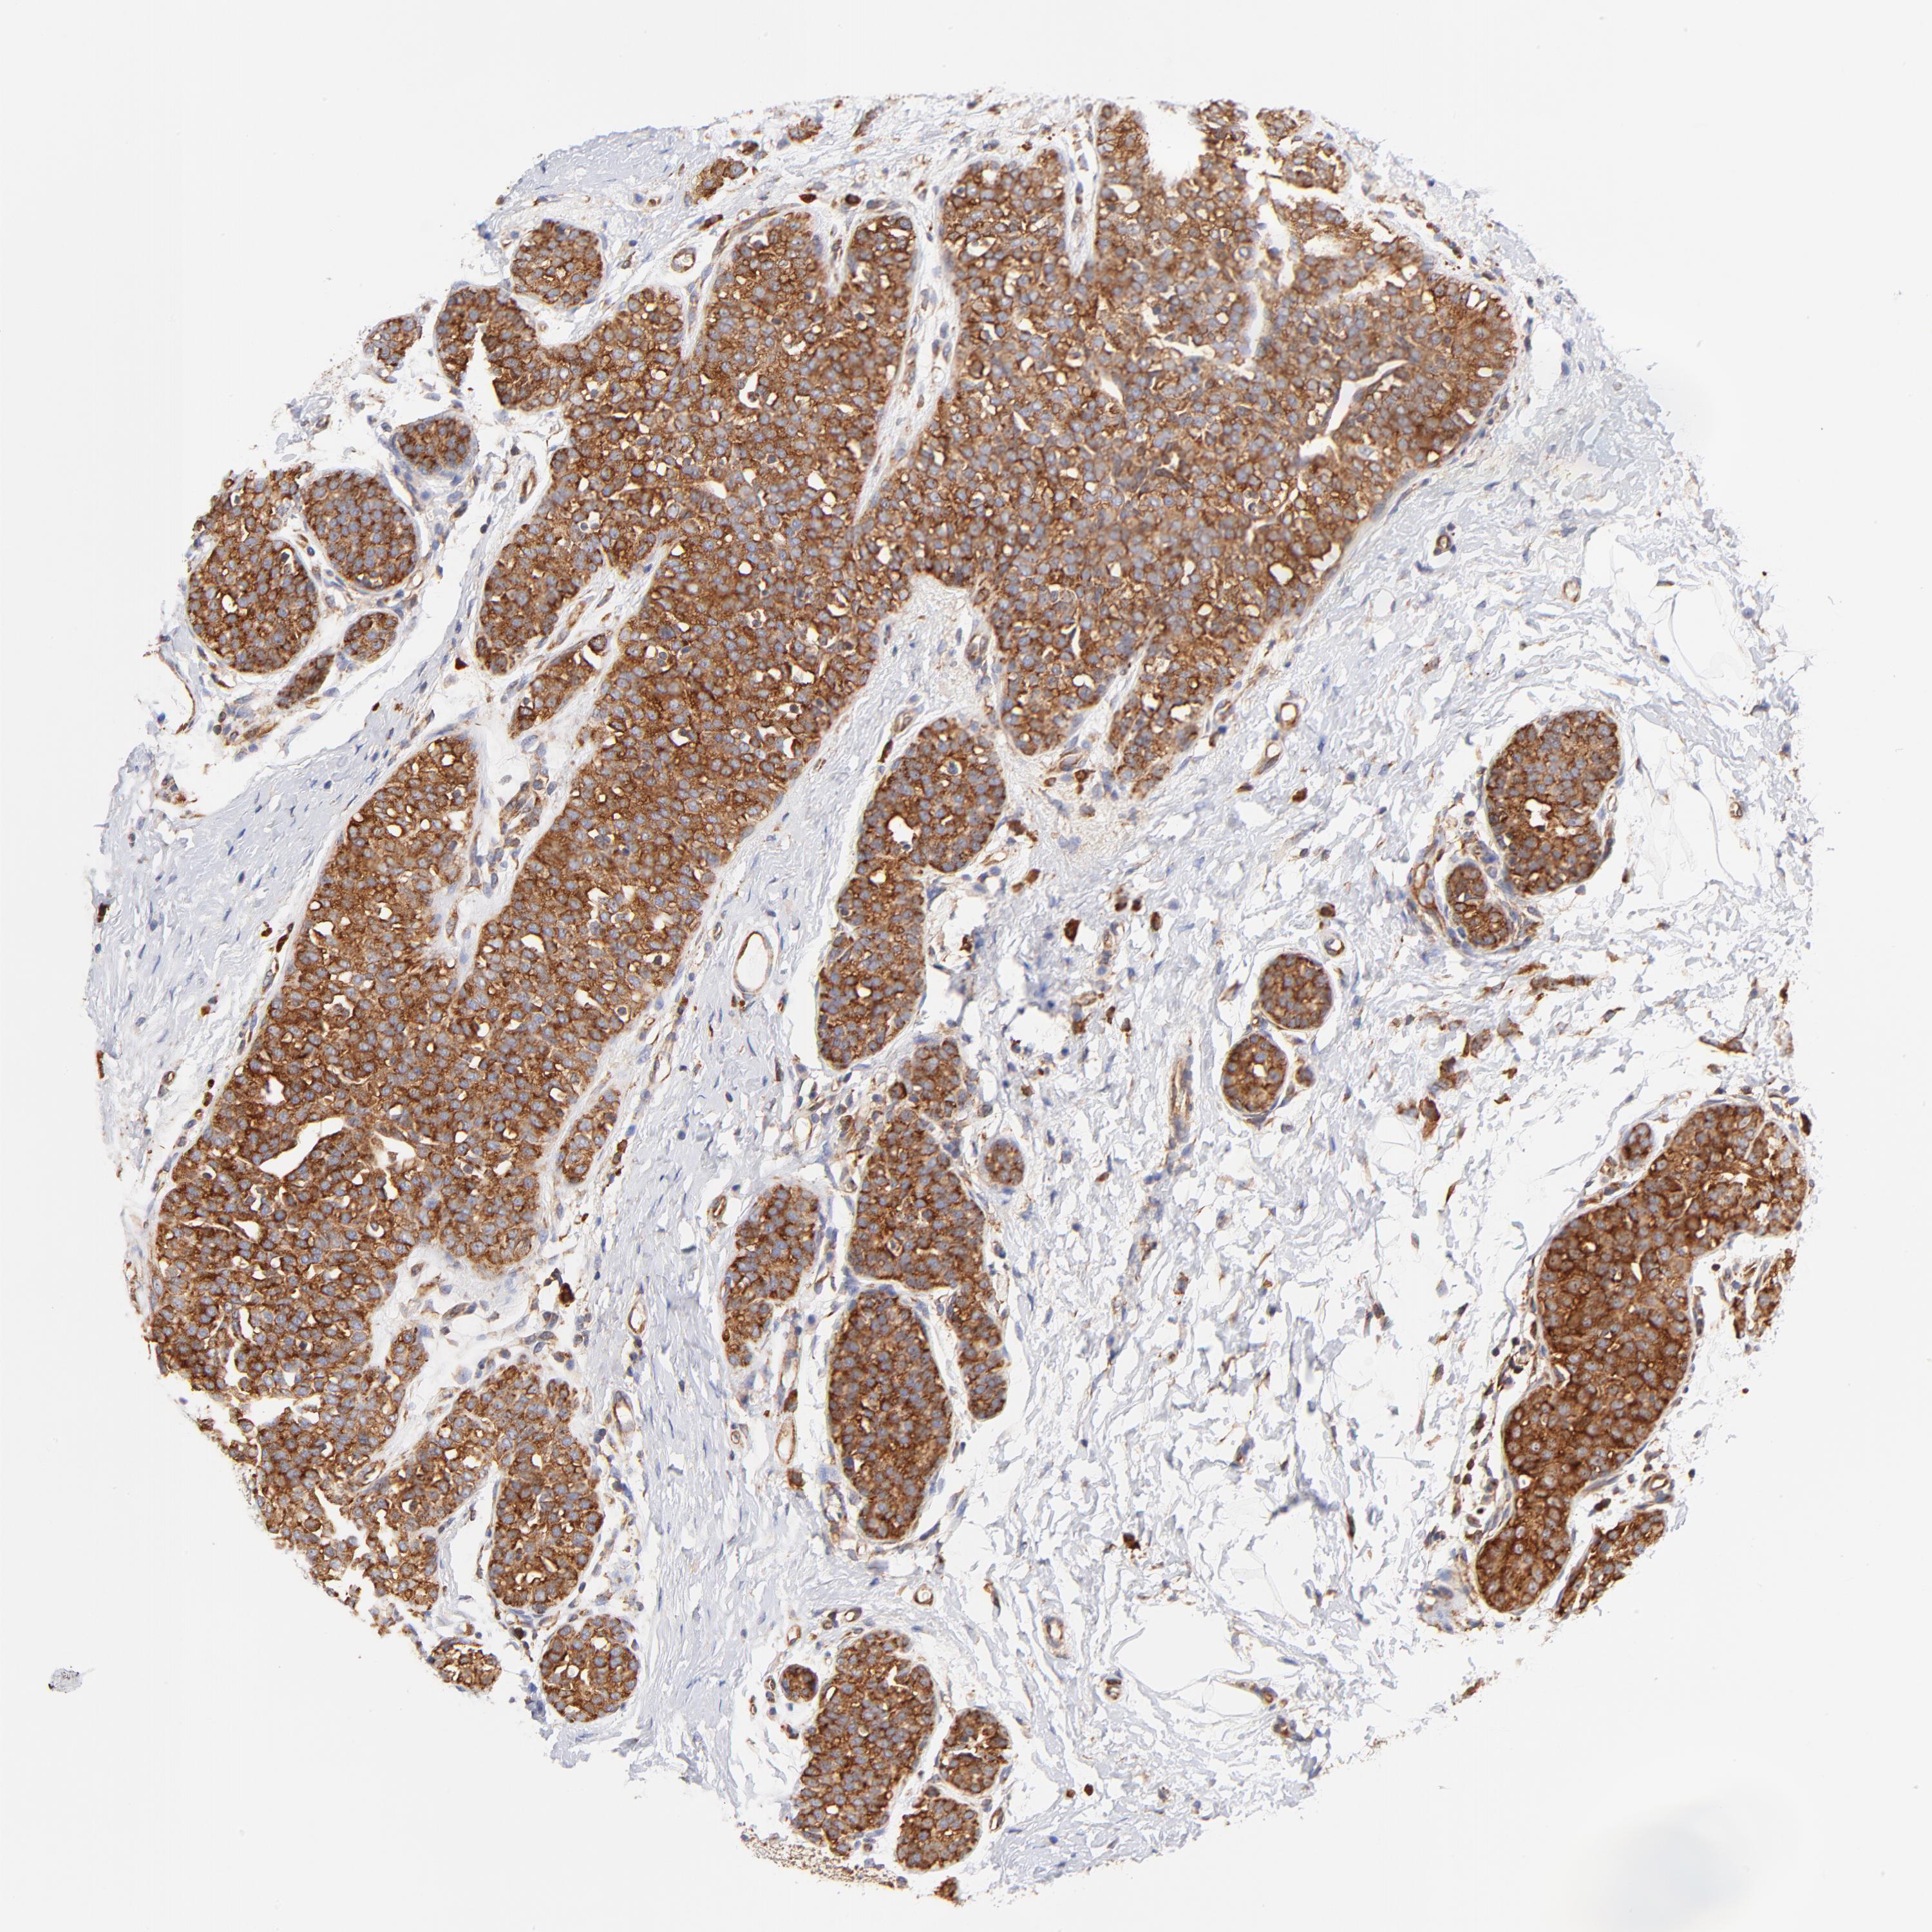

BRCA TCGA BRCA VALIDATION PROTEIN EXPRESSION

Breast cancer

Human cancer